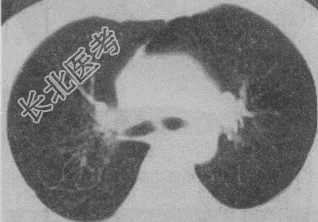

- 单项选择题患者女,23岁, 咳嗽咳痰反复发作,根据CT图像, 最可能的诊断是

A、支气管扩张并感染

B、多发肺气囊

C、多发性肺囊肿并感染

D、多发性肺脓肿

E、大叶性肺炎